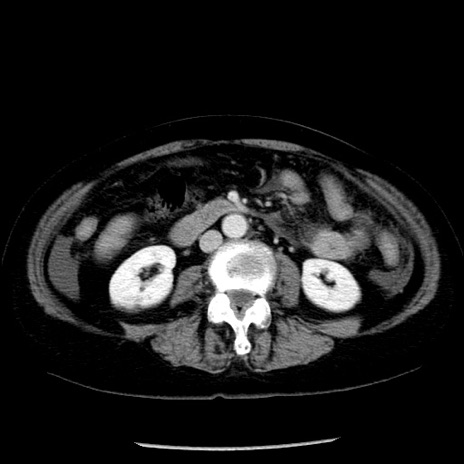

冠状断像